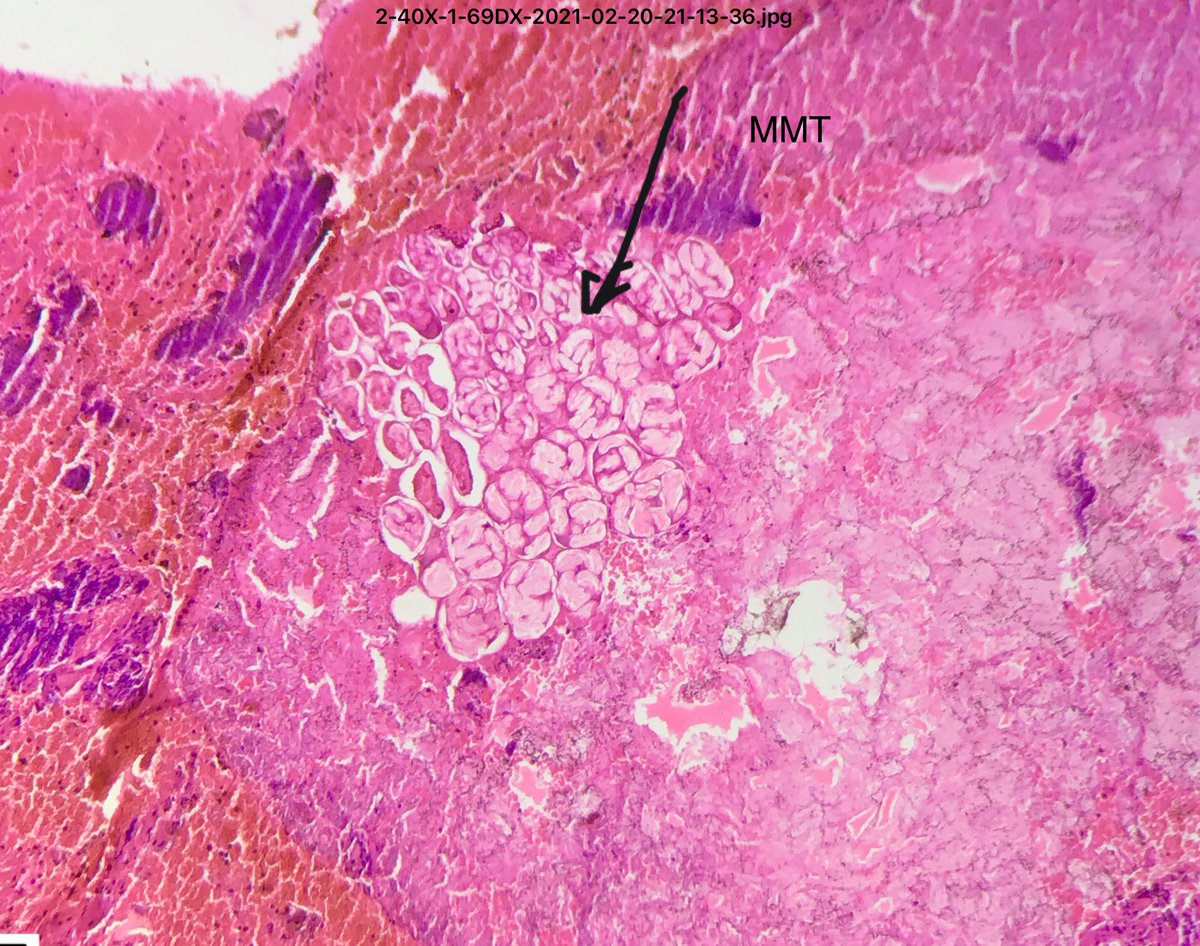

40 yo female with vaginal hemorrhage and a protruding mass from the uterine cervix. #pathology #twitterpath